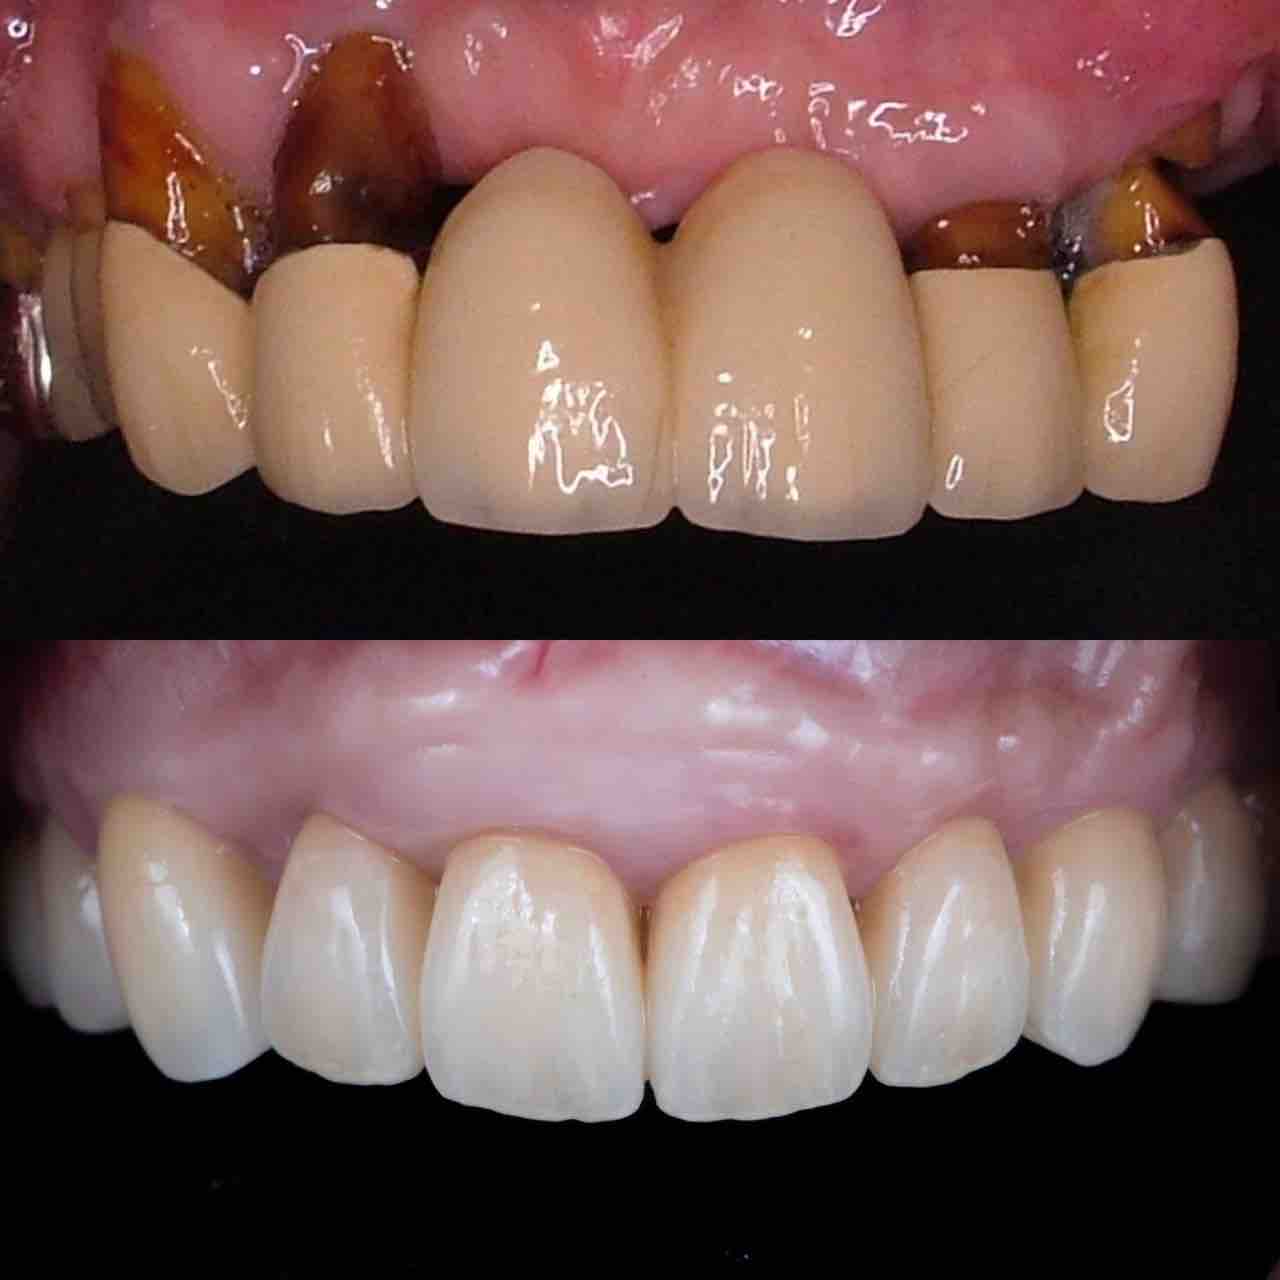

¥¤¥ó¥¹¥¿¥°¥é¥à¤ËºÜ¤»¤Æ¤¤¤ëÅö±¡¤Î¾ÉÎã¤Ç¤¹